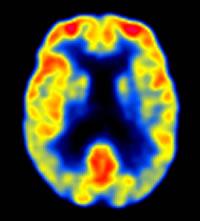

PET en Alzheimer leve © Keith A. Johnson y J. Alex Becker

A todos los sujetos participantes se les practicaron pruebas de imagen mediante PET–[18F]FDDNP, midiendo los valores de captación en las áreas de interés temporales media y lateral, del cingulado posterior, parietal, frontal y global, además de aplicarles una batería neuropsicológica para medir cinco dominios cognitivos: memoria, lenguaje, atención (y velocidad de procesamiento de la información), función ejecutiva y capacidad visoespacial. Todo ello realizado tanto basalmente (al inicio del estudio) como a los dos años de seguimiento. La captación incrementada en las regiones frontal, del cingulado posterior y global se correlacionaron con progresión del declive de la memoria a los dos años de seguimiento para todo el grupo de participantes, tanto los que ya sufrían deterioro cogntivo leve al inicio del estudio como aquellos que basalmente mostraron un envejecimiento normal. Además, se comprobó que una mayor captación basal estaba asociada a un futuro declive en la mayoría de los dominios cognitivos, incluyendo el lenguaje, atención, función ejecutiva y capacidades visoespaciales. En el grupo con deterioro cogntivo leve, la captación frontal y parietal arrojó la mayor precisión diagnóstica en la identificación de convertidores a enfermedad de Alzheimer versus no convertidores a los dos años, bastante por encima de la hipercaptación en la región temporal media. En sus conclusiones, los autores afirman que, en base a sus resultados,«Los patrones de captación regional en el PET–[18F]FDDNP son consistentes con los patrones neuropatológicos conocidos de acumulación de placas y ovillos, difundiéndose desde la región temporal media a otras regiones neocorticales a medida que progresa la enfermedad. Como los patrones de captación predicen el declive cognitivo futuro y van aumentando a lo largo del tiempo a la par que el declive cognitivo, el escaneado con PET–[18F]FDDNP puede tener utilidad práctica para identificar a personas con riesgo de futuro declive cognitivo, así como para el seguimiento de la efectividad de las intervenciones novedosas que se diseñen para prevenir o retrasar la neurodegeneración y el declive cogntivo».Referencia bibliográfica: Gary W. Small, Prabha Siddarth, Vladimir Kepe, Linda M. Ercoli, Alison C. Burggren, Susan Y. Bookheimer et al. Prediction of Cognitive Decline by Positron Emission Tomography of Brain Amyloid and Tau. Arch Neurol. 2012;69(2):215-222.